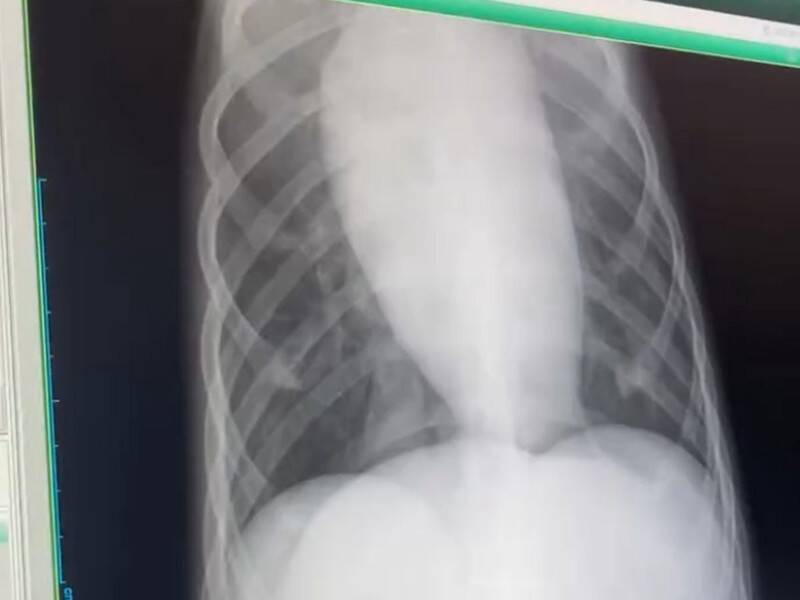

毎日楽しそうに過ごしていたというテトくんですが、フィラリア症の治療は命を落とすリスクもあり、とても過酷なものでした。駆虫薬を投与した日の夜には、心拍や呼吸が乱れたり熱が出たりして、眠ることができないほど苦しんでいたとか。